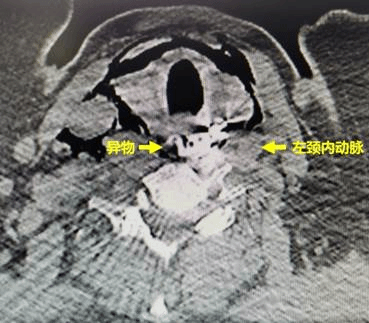

64岁的女性陈某,因误食异物(假牙)后喉部疼痛、呼吸困难,被120急救车紧急送往ac米兰官网中文网站一院急诊急救中心。胸外科常浩教授为患者检查发现异物形状特殊、位置刁钻,并且固定假牙的钢钩已刺破食管壁,引起纵隔感染,患者随时面临窒息风险。同时,钢钩毗邻左颈内动脉,随时有刺破颈部血管,导致大出血的风险,患者的生命悬于一线。

14时10分,在麻醉科李晓红医生和手术室护士的全力配合下,常浩教授、消化内科卢曦教授、耳鼻喉科姜丽教授为患者行食管探查,食管镜、胃镜下食管异物取出术。术中,常浩教授发现食管壁被刺穿,食管粘膜肿胀明显,在食管镜的帮助下为患者顺利取出异物,并为患者安放了空肠营养管,避免创伤极大的食管切开术。